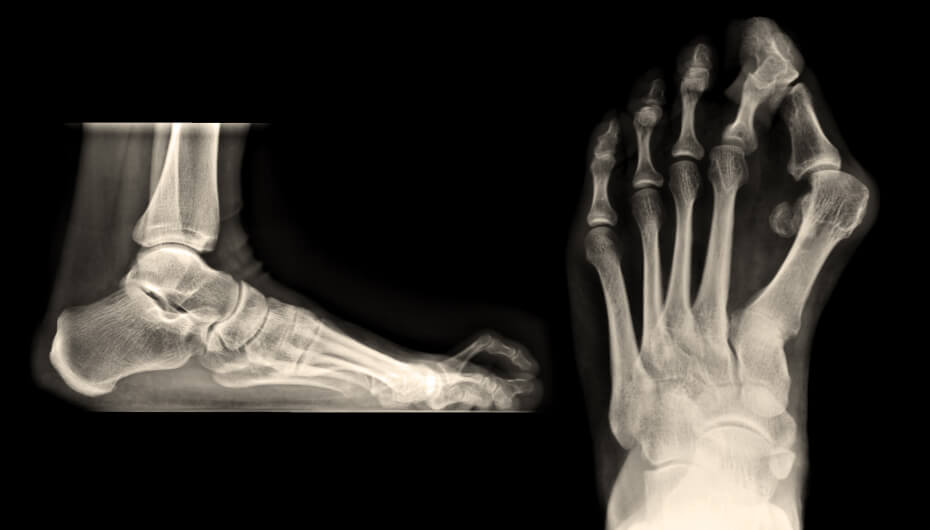

Dr. Rose Private Hospital Budapest Insight: Bunions & Hammertoes - Prevention &Treatment

The health of your feet plays a key role in everyday comfort and freedom of movement. According to Dr. Dániel Kiss, orthopaedic trauma specialist at Dr. Rose Private Hospital, bunions and hammertoes are among the most common foot deformities, yet many people only seek medical help once the condition is already causing pain. Prevention, early diagnosis, and professional treatment can not only ...